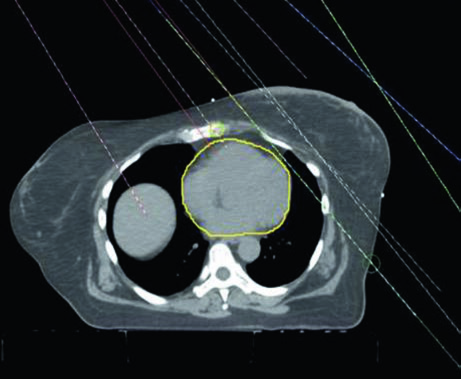

When the patient has tissue expander reconstruction, the planning geometry changes significantly. The expander protrudes the chest wall anteriorly, altering target depths and the spatial relationship with OARs. On the left side, the heart assumes a relatively more anterior position, requiring careful optimization. Figure 12.4 clearly shows the cardiac contour (yellow) in relation to the PTV in the sagittal view — this proximity explains the laterality-specific dosimetric limits.

Figure 12.5 shows axial slices for the reconstructed left chest wall. Note how the PTV encompasses the expander bilaterally and how nodal stations maintain their standard contours despite the anatomical alteration. The prosthesis itself is included in the CTV — the IMRT/VMAT criteria specify that the $D_{95\%}$ inside the implant PTV should not exceed 120% of the prescription, an essential limit to avoid damage to the prosthetic material and capsular complications. In practice, hot spots above 120% over silicone or saline expanders can cause accelerated encapsulation and complicate subsequent reconstructive surgeries.